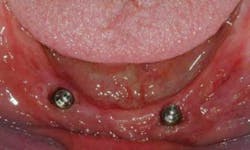

Either two standard diameter implants (~4mm in diameter) placed in the canine areas (Figs. 1 to 5), or four small diameter implants (~1.8-2.9 mm in diameter) (Figs. 6, 7) spaced from canine to canine, will solve most of your frustrations with mandibular dentures.

- When I'm treatment planning for mandibular complete dentures, my primary suggestion to patients is inclusion of at least two standard diameter implants or four small diameter implants as previously discussed.